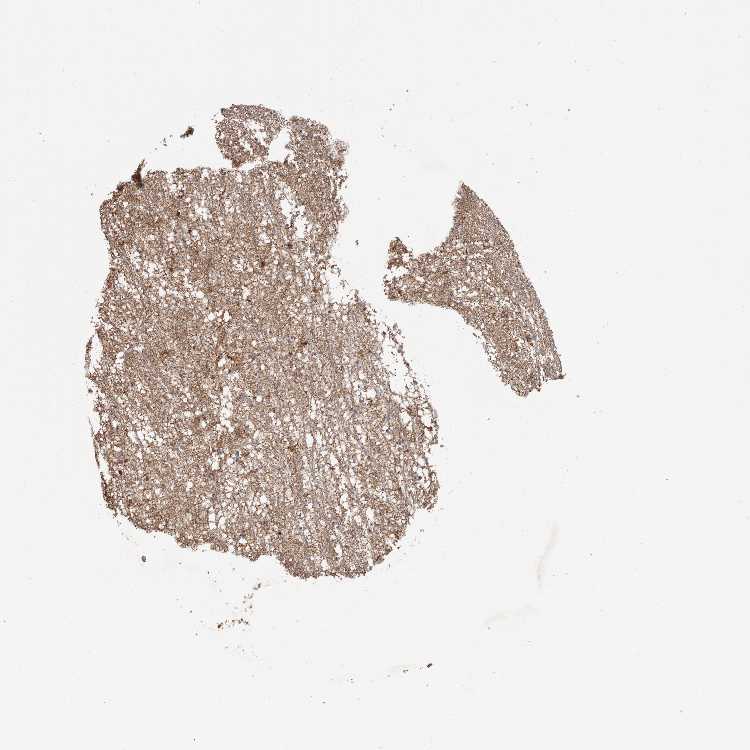

HIPPOCAMPUS - Antibody stainingi

Antibody staining in the annotated cell types in the current human tissue is reported as not detected, low, medium, or high, based on conventional immunohistochemistry profiling in selected tissues. This score is based on the combination of the staining intensity and fraction of stained cells.

Each image is clickable and will lead to virtual microscopy that enables deeper exploration of all samples and also displays staining intensity scores, fraction scores and subcellular localization as well as patient and tissue information for each sample.

Antibody HPA029715Antibody HPA029716

Glial cells Not detectedMedium

Neuronal cells MediumHigh